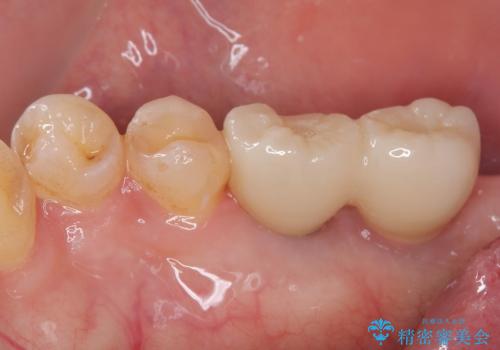

- 以前抜歯をして歯がないところにインプラント治療をしたいと来院された患者様です。

1年くらい前に他院で抜歯をしたそうです。

レントゲンで確認すると骨は十分にあるので通法通りインプラントによる補綴治療を行いました。